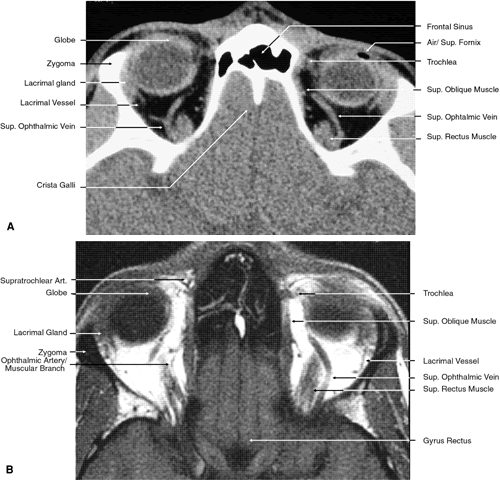

The globe is shown in Figure 12. The orbit and periorbital structures are shown in Figures 13 through 16, and the optic canal is shown in Figures 17 through 26. The cavernous sinus and optic chiasm are shown in Figures 27 and 28, and the posterior visual pathway and cranial nerves are shown in Figures 29 through 33.

Fig. 17. Coronal images through anterior orbit. A. Computed tomography scan. B. T1-weighted magnetic resonance imaging.

Fig. 18. Coronal images through midglobe. A. Computed tomography scan. B. T1-weighted magnetic resonance imaging.

Fig. 19. Coronal images through midorbit posterior to the globe. A. Computed tomography scan.B. T1-weighted magnetic resonance imaging.

Fig. 20. Coronal images through orbital apex. A. Computed tomography scan. B. T1-weighted magnetic resonance imaging. C. Anatomic section of a cadaver head at the level of the orbital apex.

Fig. 21. Coronal images through optic canal. A. Computed tomography scan. B. T1-weighted magnetic resonance imaging.

Fig. 22. Axial images at the level of inferior orbit. A. Computed tomography scan. B. T1-weighted magnetic resonance imaging.

Fig. 23. Axial images at the level of midorbit. A. Computed tomography scan. B. T1-weighted magnetic resonance imaging.

Fig. 24. Axial images at the level of superior orbit. A. Computed tomography scan. B. T1-weighted magnetic resonance imaging.

Fig. 25. Axial images at the level of tendon of the superior oblique. A. Computed tomography scan. B. T1-weighted magnetic resonance imaging.